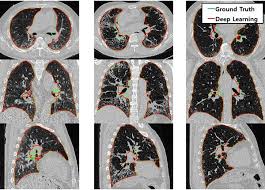

- X-ray, CT, MRI, PET 등 의료영상 데이터를 수집 및 분석

- AI 알고리즘을 활용한 질병 진단 모델 개발

- 병변(종양, 골절, 혈관 이상 등) 자동 탐지 시스템 연구

- 딥러닝·CNN(합성곱 신경망) 기반 진단 모델 설계

- 의료기관과 협력하여 실제 진단 결과 비교 검증